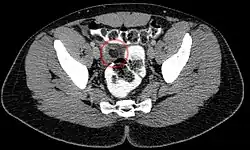

Ultrasound and CT scans are the normal means of positive diagnosis of epiploic appendagitis. Ultrasound scans show "an oval, non-compressible hyperechoic mass with a subtle hypoechoic rim directly under the site of maximum tenderness".[4] Normally, epiploic appendages cannot be seen on CT scan.[4] After cross-sectional imaging and the increased use of abdominal CT for evaluating lower abdominal pain, EA is increasingly diagnosed. Pathognomonic CT scan data represent EA as 2–4 cm, oval shaped, fat density lesions, surrounded by inflammation. Contrasting with diverticulitis findings, the colonic wall is mostly unchanged.